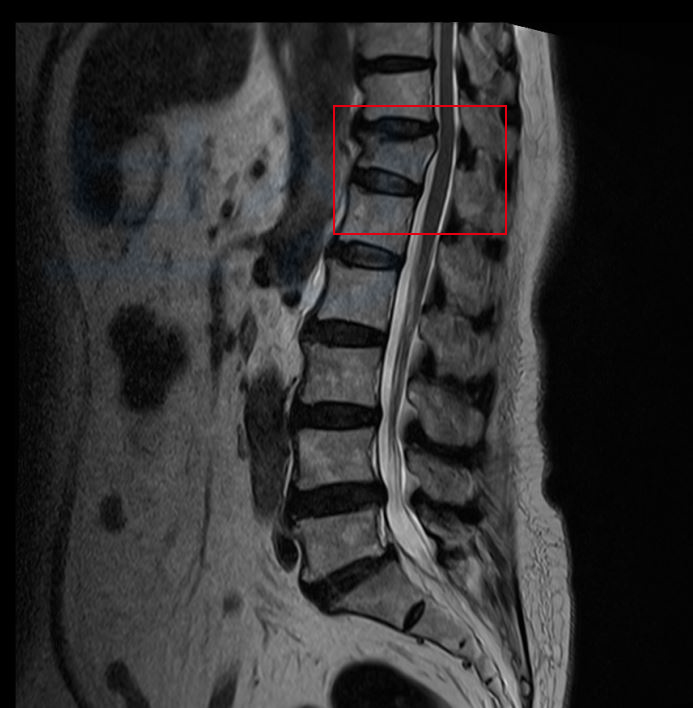

의뢰인은 환경 미화원으로 일하시면서 바닥을 물걸레질 하시다 미끄러져 넘어지는 사고를 당하셨습니다. 그런데 이 사고로 의뢰인은 허리에 극심한 통증을 호소하셨고 병원에 내원하여 정밀검사를 받아보니 흉추12번 압박골절 진단을 받으셨죠.